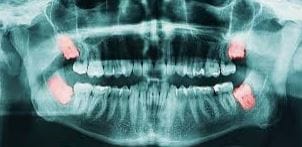

Tengo 23 años y la semana pasada comencé a sentir un hormigueo en los dientes delanteros superiores, luego sentí algo de dolor. Fui al dentista y me dijo que eran las muelas de juicio. Me hice una placa y me dijeron que estaban saliendo bien, por lo que podía ser algo anímico. Me dijeron que mis encías estaban bien. También consulté por una pequeña movilidad en las paletas. Es imperceptible a la vista, pero me preocupa porque la siento al apoyar con fuerza la lengua sobre los dientes. ¿Debería volver a ir al odontólogo o se trata de algo normal?

es esa la tuya?